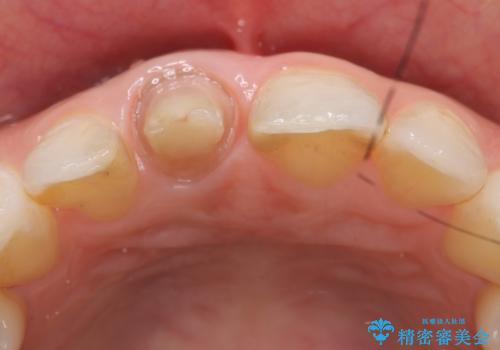

- 右上1番目の歯の変色が気になると来院された方の症例です。

検査の結果、右上1の歯は失活(歯の神経が死んでいること)していたため根管治療を行いました。

その後オールセラミッククラウン(スペシャル)による補綴を行いました。

今回用いたオールセラミッククラウンはジルコニアフレームという白い素材の上にセラミックを盛っているため、審美性が非常に高いのが特徴です。

また、ジルコニアは人工ダイヤモンドの材料にも使われているほど高い強度を持っており、そのためオールセラミッククラウンは審美性だけでなく、奥歯やブリッジの補綴も可能とするクラウンです。